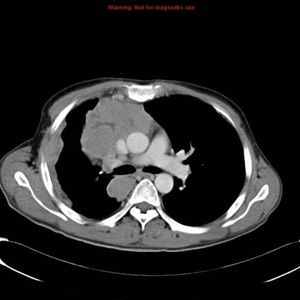

Dysphagia

Cough

Dyspnea

Sarcoidosis..?

Lung cancer ?